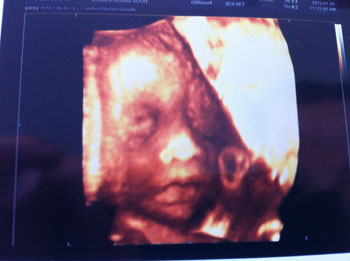

違う写真、もう一枚。この写真は少しはおしとやかな女の子に見えるかしらぁ?旦那は私に似ているね喜んでいるのですが、私としては嬉しくない!(笑)もっとかわいく産まれてきてほしいという、母の欲望(笑)でも、元気で産まれてきてくれれば、それで良し!

果たして、クルクリは誰に似てるんだろうな。今のところ、じいちゃんOR私の二択であるが……汗。